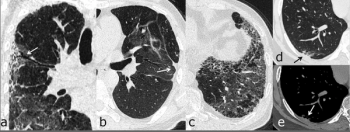

Research data reveals using LDCT with patients who have never smoked – but who are still at high risk – is effective for lung cancer screening.